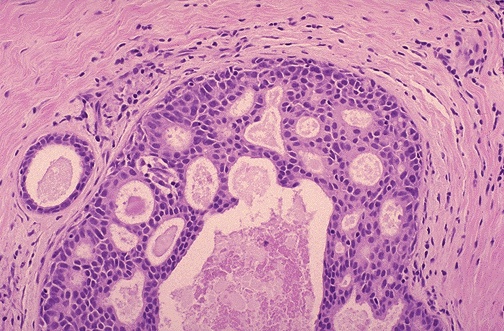

| The classic cribriform pattern of intraductal carcinoma of the breast is shown here. The neoplastic epithelial cells within the duct show minimal hyperchromatism and pleomorphism, but they surround holes with sharp margins, as though punched out by a cookie cutter. |